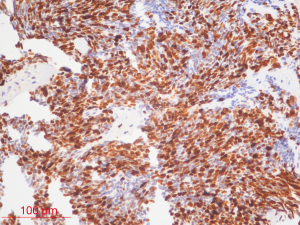

The inclusion criteria were as follows: (I) patients with available pathology (after resection); (II) patients with preoperative MRI data (see Figures 1,2); (III) patients with proven expression of the Ki-67 index by immunohistochemistry; Ki-67 index greater than or equal to 30% is defined as high expression, and Ki-67 index less than 30% is defined as low expression (see Figures 3,4); (IV) patients aged less than 18 years. A total of 271 patients were screened, and 181 patients were excluded due to the following reasons: (I) patients lacking Ki-67 expression by immunohistochemistry (n=96); (II) patients lacking at least one of the following MRI sequences: T1-weighted images (T1W), T2-weighted images (T2W), and contrast-enhanced T1-weighted images (CE-T1W) (n=71); and (III) patients with MR images that had motion or other kinds of artifacts that may affect subsequent segmentation and analysis (n=14). Finally, 90 subjects met the requirements and were included in this study (22 cases of Ki-67 index ≤30 and 68 cases of Ki-67 index >30). Clinical information (age and sex) and tumor characteristics (location, pathological type, and molecular type) are summarized in Table 1.

Ki-67 index is a nuclear antigen related to proliferating cells. Its function is closely related to mitosis and is indispensable in cell proliferation. At present, clinical immunohistochemistry techniques are used to detect the expression of Ki-67 protein, and its positive staining indicates that cancer cells are proliferating actively. It can be used to evaluate the differentiation status of MB cells at the molecular biology level. Compared with traditional pathological classification, this indicator is more objective and easier to implement.